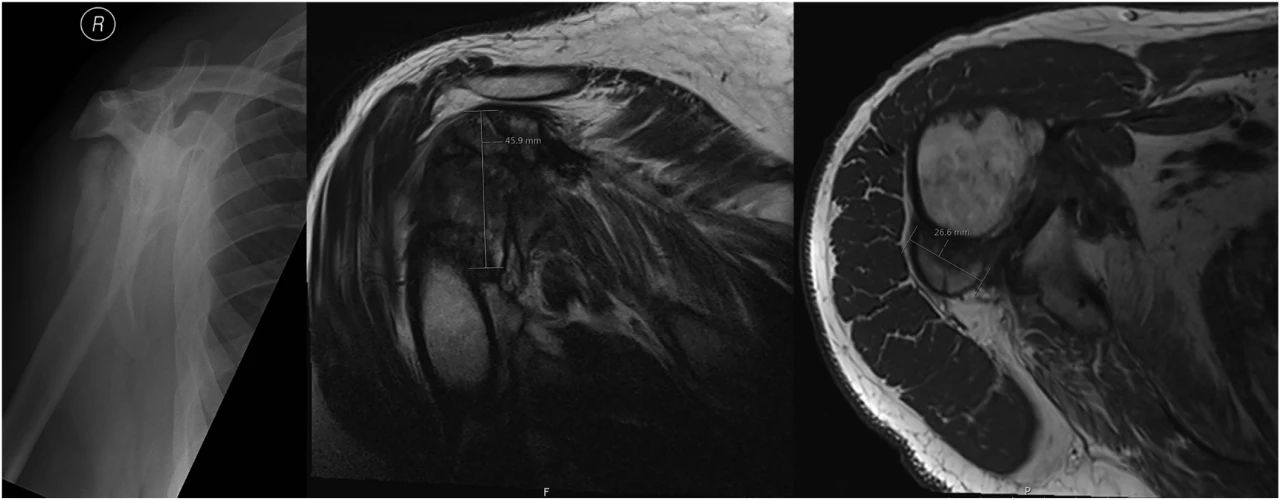

MRI检查

MRI 具有良好的软组织对比度,表现与疾病的时间相关,并且与其他影像平行,急性期 ,主要为软组织肿块合并周围水肿,病灶在 T1WI 上与肌肉呈等信号或稍高信号,在 T2WI 上以高信号为主。中期,T1WI 和 T2WI 信号都可减低,可以在病灶内部看到扭曲了的长T1 脂肪层,病灶边缘的钙化表现为低信号环,后期低信号环将越来越清楚,这也是异位骨化的特征性表现之一;此时 X 线平片可以看到皮质边缘。

后期,界限清楚的信号不均匀肿块,无水肿,在肿块中心可以 T1 呈高信号,表示脂肪化的黄骨髓形成,外围一圈 T1、T2 扭曲的低信号,代表骨化的皮质骨,此时期 MRI 的诊断价值不如 X 线和 CT,需要结合二者观察。

早期异位骨化:该患者颅脑损伤并且合并膝关节创伤,首次检查(a-d)股内侧肌周围T1高信号,皮下脂肪水肿,压脂呈花边样改变;3 周后复查(e-f)病灶内层不均匀强化,平片可以看到骨化及骨膜反应。

晚期异位骨化:患者受伤后 9 个月因关节强直复查,注意病灶周边清楚的低信号环。